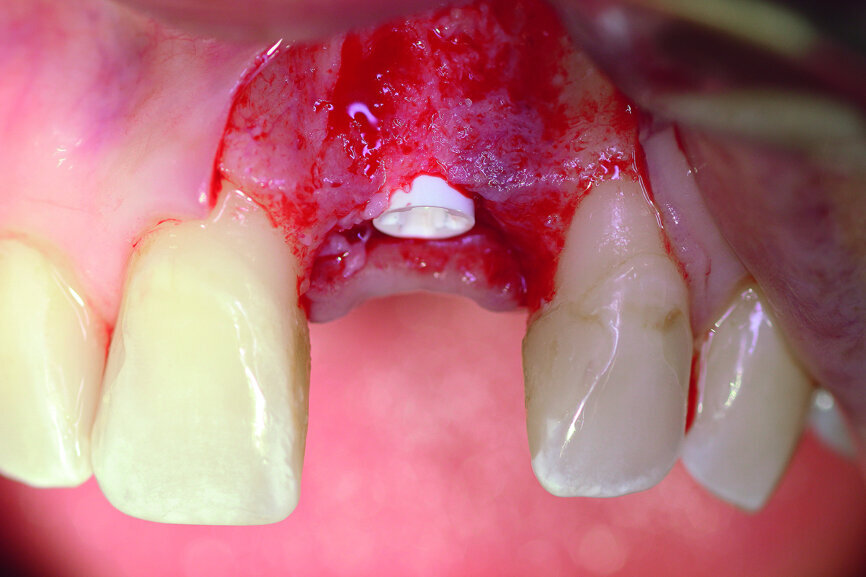

After extraction of tooth #21, the apical granulation tissue was excochleated through a semilunar incision (Fig. 3). A two-stage procedure was performed to prevent failure of osseointegration of the ceramic implant and to preserve the soft-tissue structures (papillae and attached gingiva). A claspless prosthesis made from Valplast (Valplast International) served as a temporary restoration. The implant site in region #21 was uncovered after five months (Fig. 4). A two-piece ceramic implant (diameter: 4.2 mm; length: 12.0 mm) was then inserted (Figs. 5a & b). The guidelines for implant placement in the aesthetic zone and the drilling procedure specified by the manufacturer were observed.13, 14 Both vertical and transverse insertion depth are decisive for prosthetic success. The implant can be placed between 1.6 mm and 0.6 mm supracrestally because of a special thermal etching procedure in the collar region; the insertion depth is determined by the gingival height and the existing bone of the adjacent teeth. The implant positioning should be approximately 2–3 mm subgingivally because the abutments are added 1 mm above implant shoulder level. Transversal bone augmentation was performed with a mixture of autogenous bone chips (retrieved from the retromolar mandible), xenograft (Geistlich Bio-Oss, Geistlich Biomaterials) and guided bone regeneration (Jason membrane, botiss biomaterials; Figs. 6a & b). The exposure was performed after four months using a PEEK gingiva former (Fig. 7).

Fig. 5a: A two-piece ceramic implant was inserted.

Fig. 5b: A two-piece ceramic implant was inserted.